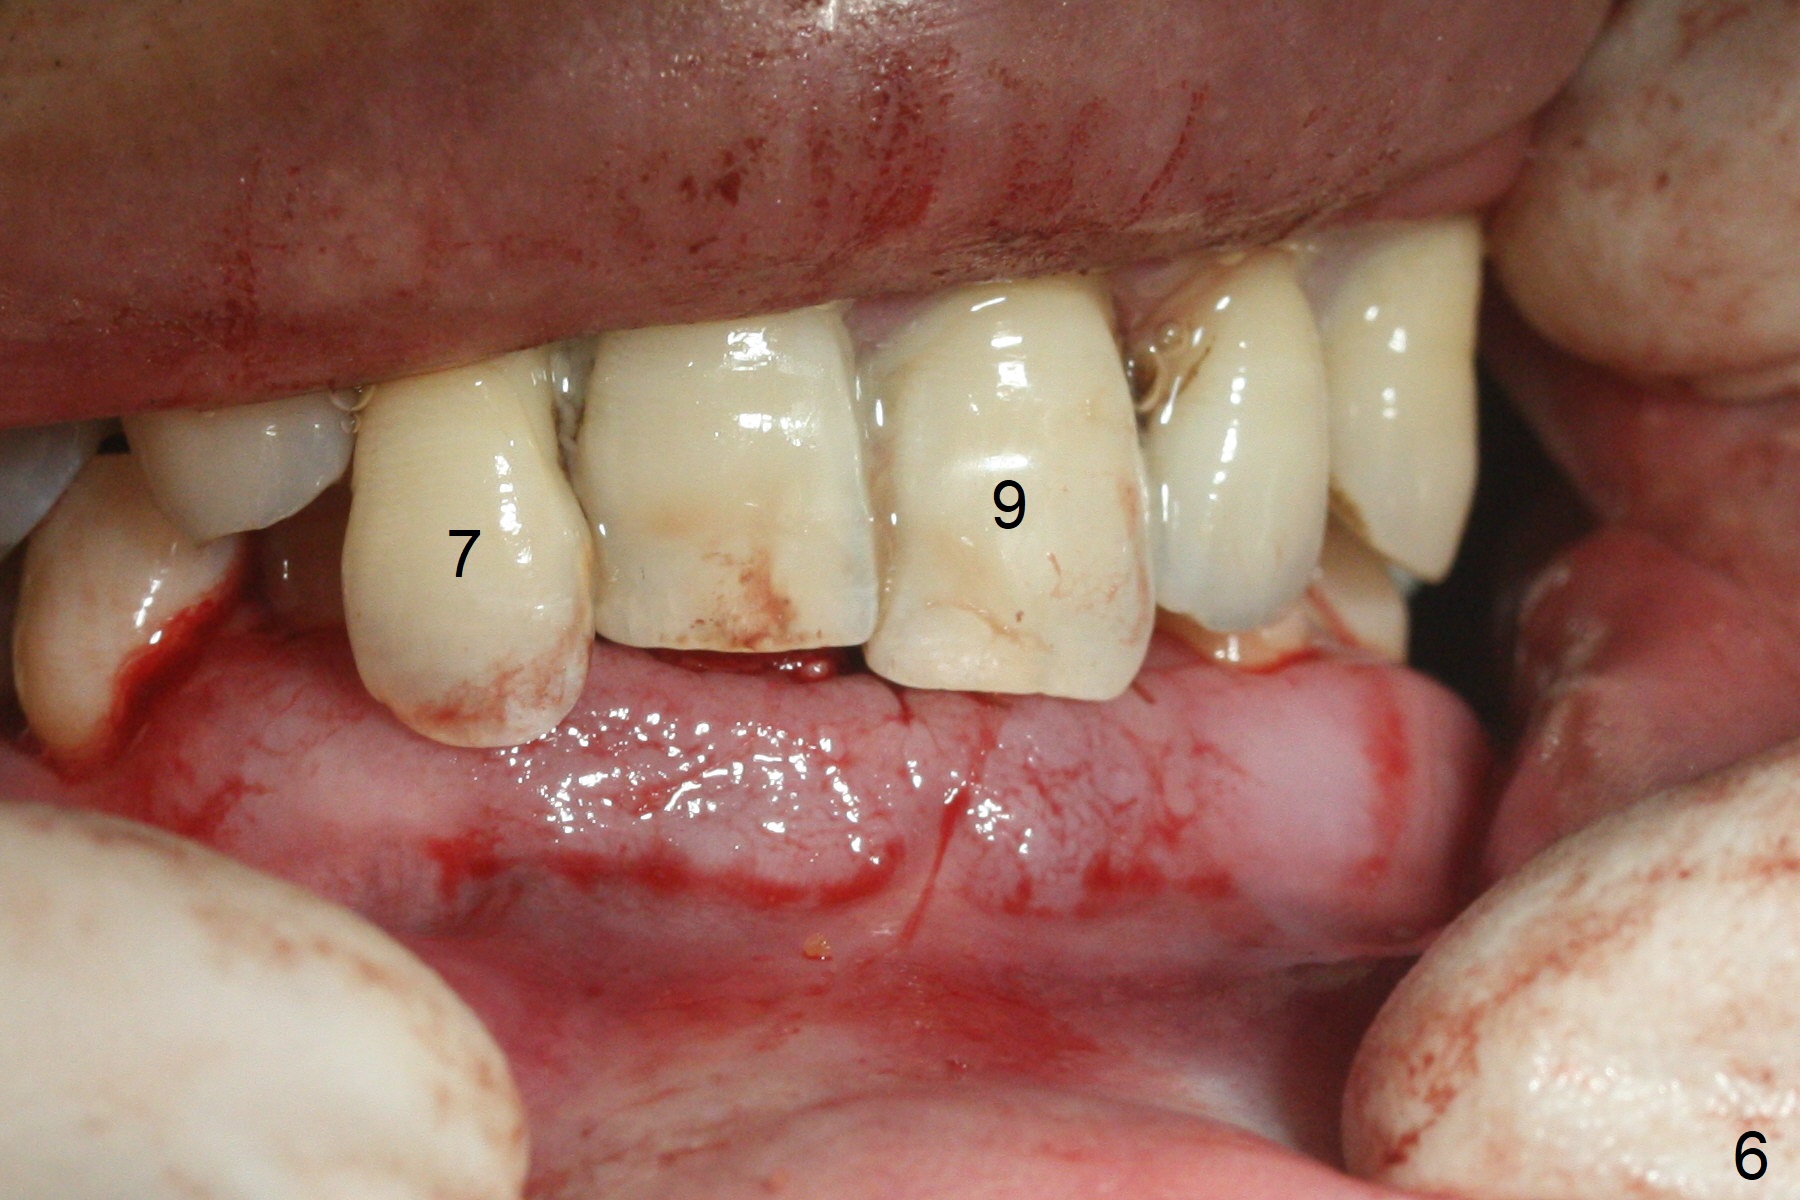

After extraction of 4 of the lower incisors, there are basically 2 sockets (#23/24 and 25/26), separated by the apparently midline bone (Fig.1 red line).  In spite of using Lindamann bur to move the 25/26 osteotomy mesially, a 3x14(2) mm dummy implant remains close to the tooth #27 (Fig.2).  The terminal branch of the Incisive Canal (<) is located between the lateral and central incisors.  A de novo osteotomy (Fig.3 (1.5 mm drill)) is made mesial to the original one (O).  While the 3x14(2) mm dummy implant is incompletely placed at #25/26, a 3x14(4) mm 1-piece one is placed at #23/24 (Fig.4).  Finally the same implant is placed at #25/26 with placement of mineralized cortical/cancellous bone (Fig.5 *).  When the large sockets are sutured, the supraerupted teeth #7-9 touch the lower gingiva (Fig.6).  The incisal edge is reduced for clearance (Fig.7).  Periodontal dressing is less likely to be dislodged with the incisal edge reduction (Fig.8,9).  A provisional FPD is fabricated 1 week postop.  Hard (Fig.10) and soft (Fig.11,12) tissues heal 5.5 months postop.  The patient returns for crown cementation 3 months post impression (9 months postop, Fig.13,14).